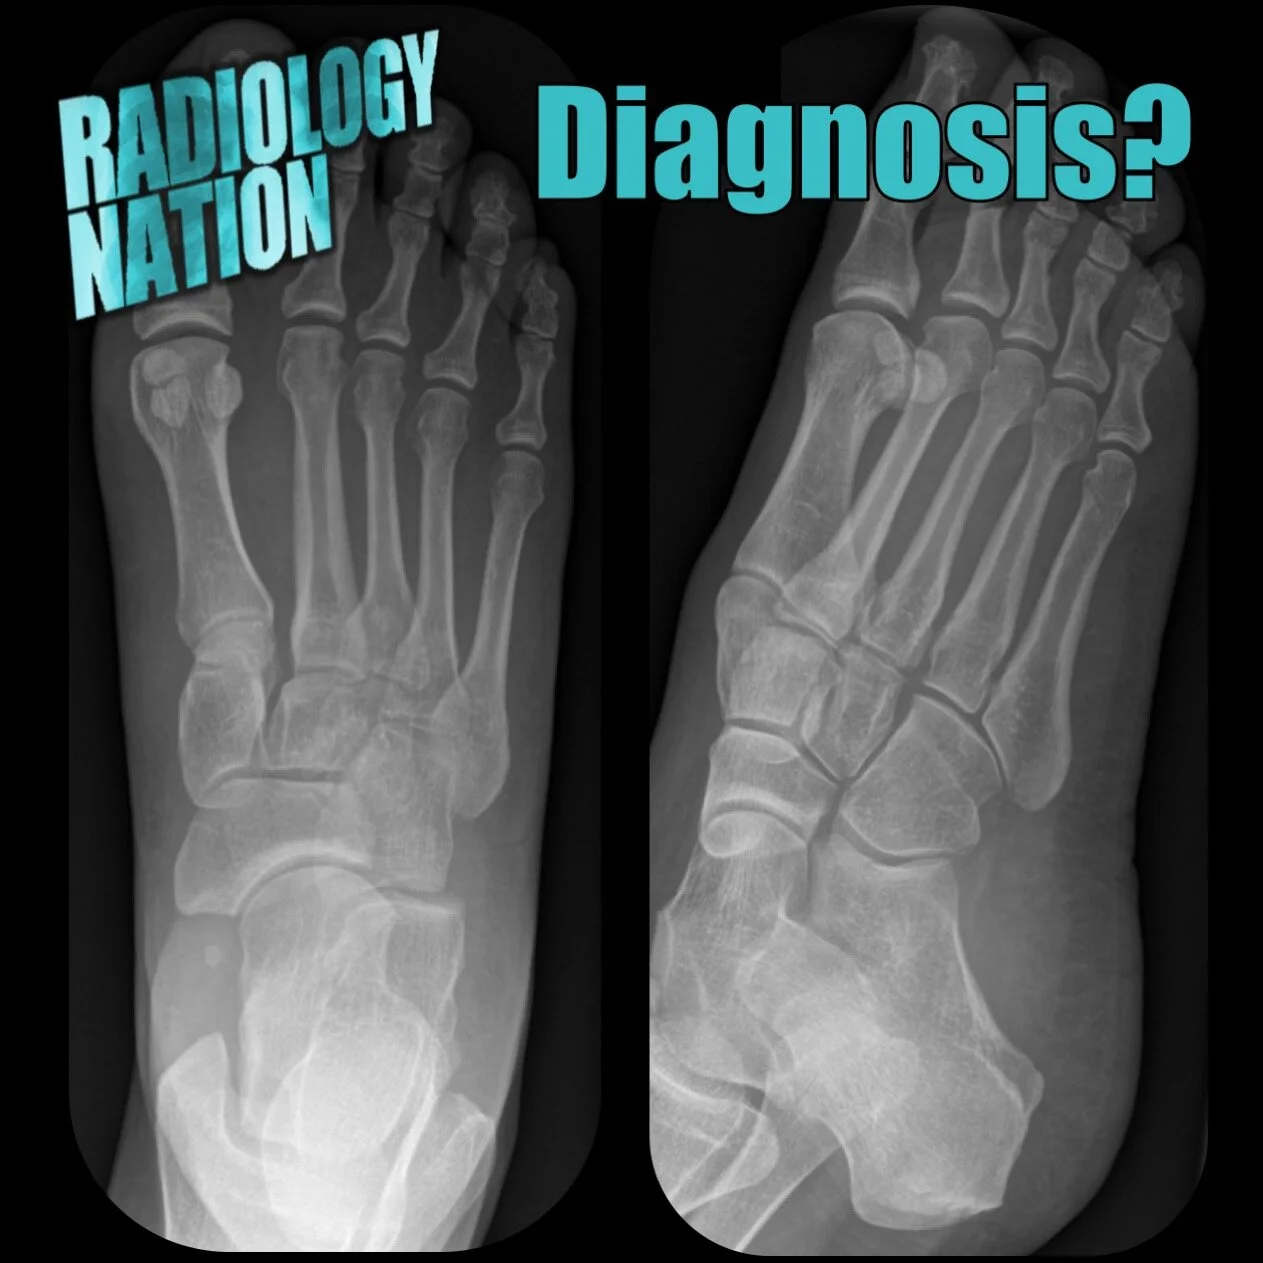

Musculoskeletal Radiographs

Visual guides to radiographic image interpretation

Musculoskeletal Radiology Tutorials

On this page we have a series of image based tutorials for you to teach yourself musculoskeletal radiology!